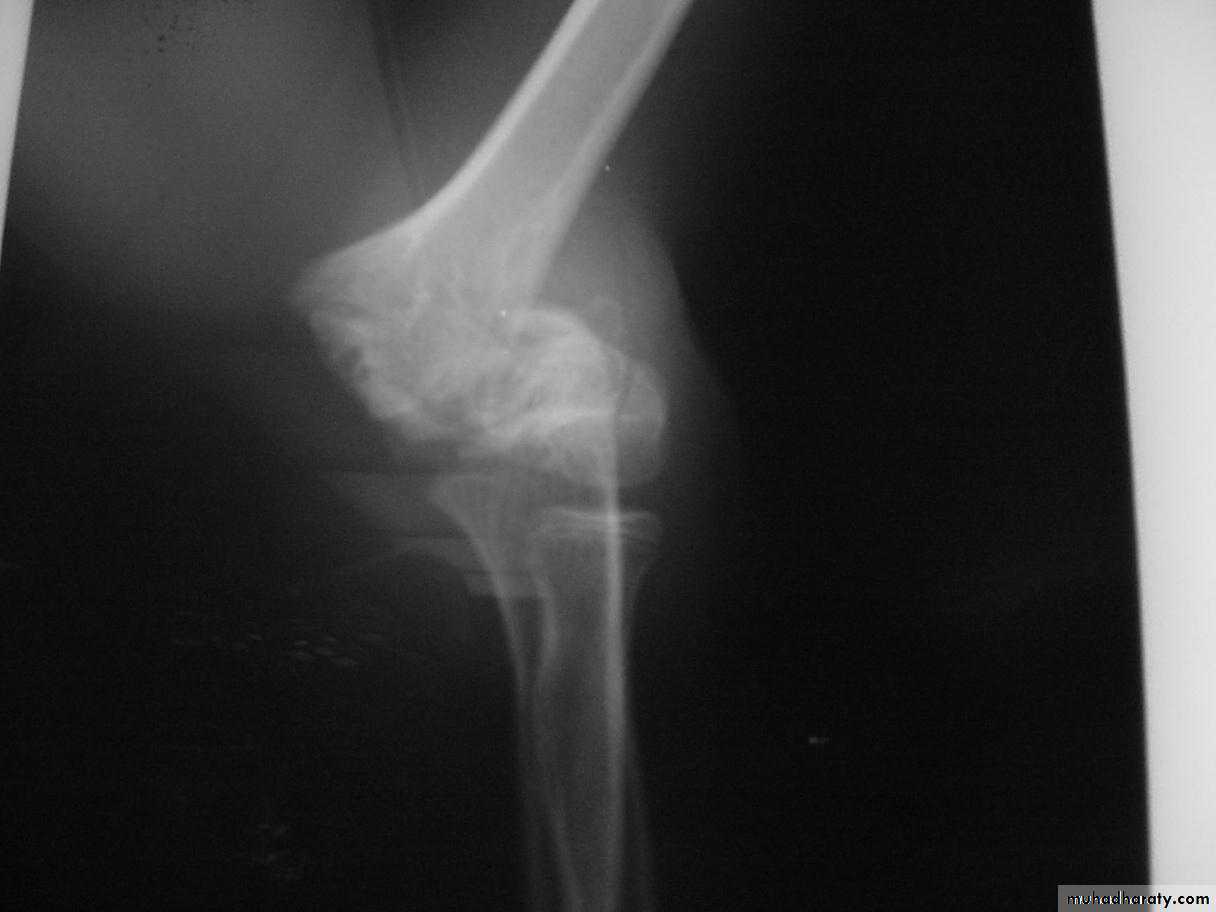

This classical Type III pattern

is obviously a flexion injury.With these one needs to be

prepared to do an open reduction !!

8 y.o.

Is this a simple extension

type supracondylar fracture ??

It also has

anterolatateraldisplacement !!

The distal fragment is

not flexed,but also it is not extended to any degree.

This also is a Type III Flexion Pattern.